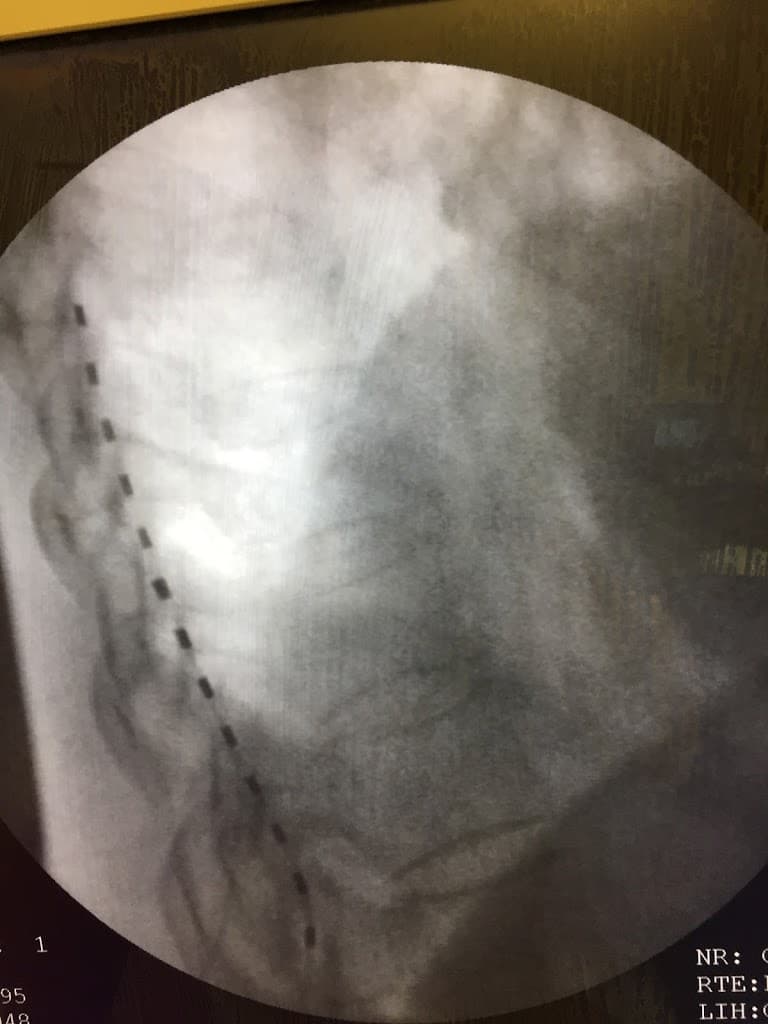

Spinal Cord Stimulation

Implantable devices to manage chronic pain

Injection Therapy

Corticosteroid and other therapeutic injections for pain relief